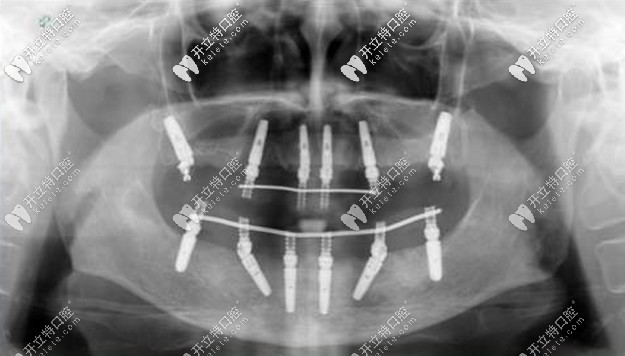

老人種牙All-on-4全口種植牙——價(jià)格在16萬(wàn)-25萬(wàn)之間,上下牙各四顆種植釘,利用8個(gè)植體就可以變好全口牙齒的咀嚼功能,種植顆數(shù)少,相比柵欄式種植更加便宜。

allon4全口種植牙

老人種植All-on-6全口種植牙——價(jià)格在20萬(wàn)-30萬(wàn)之間,上下牙各6個(gè)人工牙根,是All-on-4全口種植牙的升級(jí)版,比較適合牙槽骨萎縮的缺牙者,由于四個(gè)種植釘無(wú)法支撐半個(gè)口腔的咬合力,所以要增加到6個(gè)。

All-on-6全口種植牙